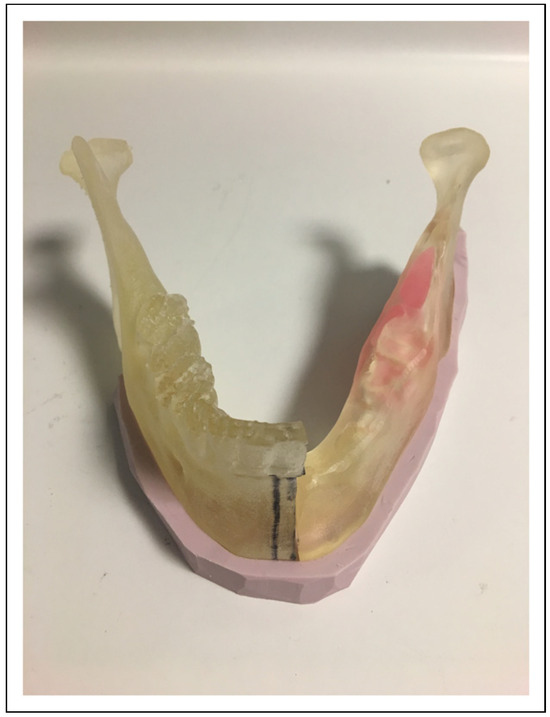

Extended Total Temporomandibular Joint Replacement—A Feasible Option for Functional and Aesthetic Reconstruction of Mandibular Defects Involving the Temporomandibular Joint

Case Examples

- Two-stage regime with simultaneous bone graft, patient 5

Two-Stage Regime, Patient 1

Single-Stage Regime, Patient 10

Bilateral TMJ Replacement With Complete Replacement of the Mandible, Patient 8